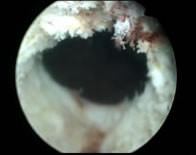

Existen cirujanos que antes de empezar con la vaporización realizan una incisión en el cuello vesical (Fig. 4), siempre con cuidado de no enterrar la punta de la fibra en el tejido. En caso de que la próstata tenga un lóbulo medio bien definido, se pueden realizar dos incisiones a las 5 y 7 horarias.

| Incisión del cuello vesical | |

![]() |

| Fig.4 | |

| La incisión en el cuello vesical proporciona las siguientes ventajas: | |

| * Mejora la irrigación a través de la próstata | |

| * proporciona mejor visualización | |

| * Permite la identificación de las fibras del cuello vesical y de la cápsula prostática | |